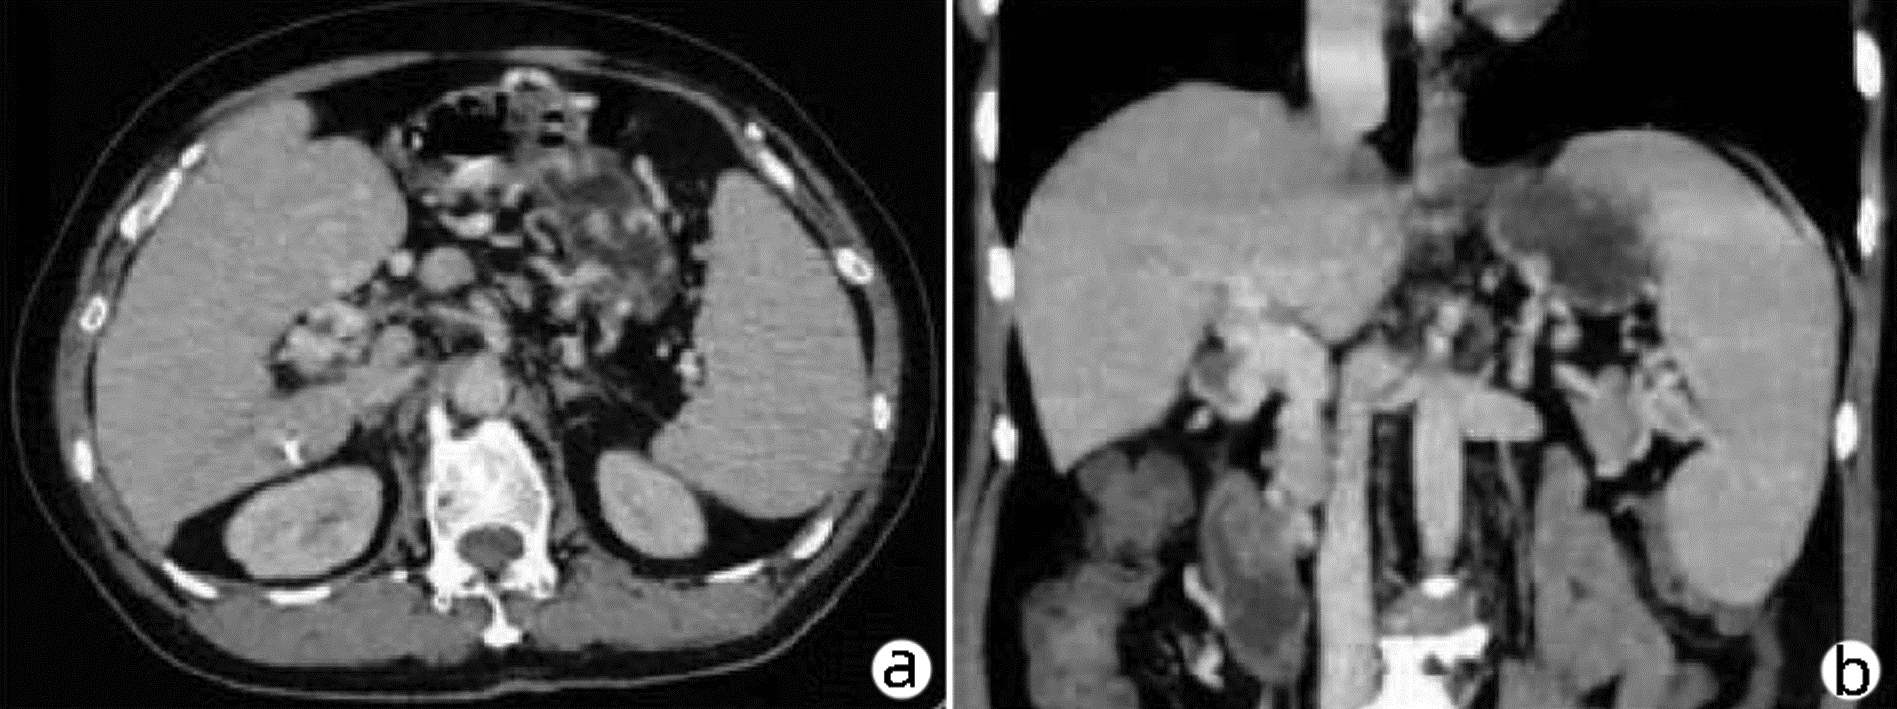

多学科联合诊疗原发性肝脏神经内分泌瘤1例报告

赵凯越, 严哲, 黄缘

2023, 39(6): 1411-1413. DOI: 10.3969/j.issn.1001-5256.2023.06.024

摘要(795) HTML (186) PDF (2153KB)(63)

摘要: